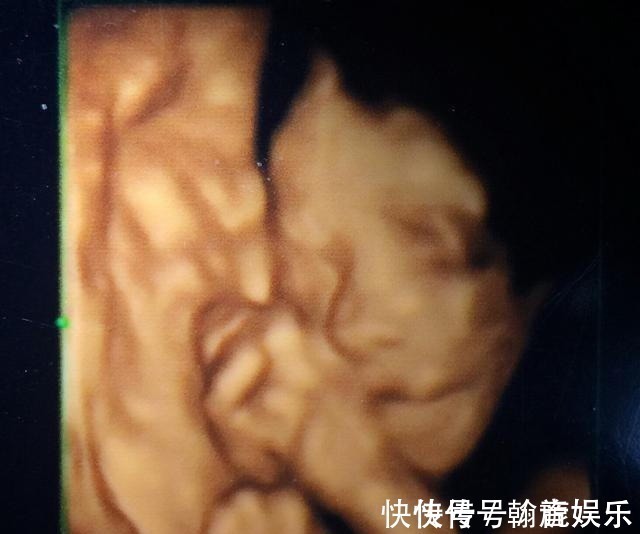

胎儿|孕期要做四维彩超,四维彩超的这些误区和认识,孕妈妈早知道早好

近年来,四维彩超开展得如火如荼,逐渐深入人心,但是很多孕妈妈对四维彩超在认识上还是有些误区,经常接到关于四维彩超的提问。

文章插图